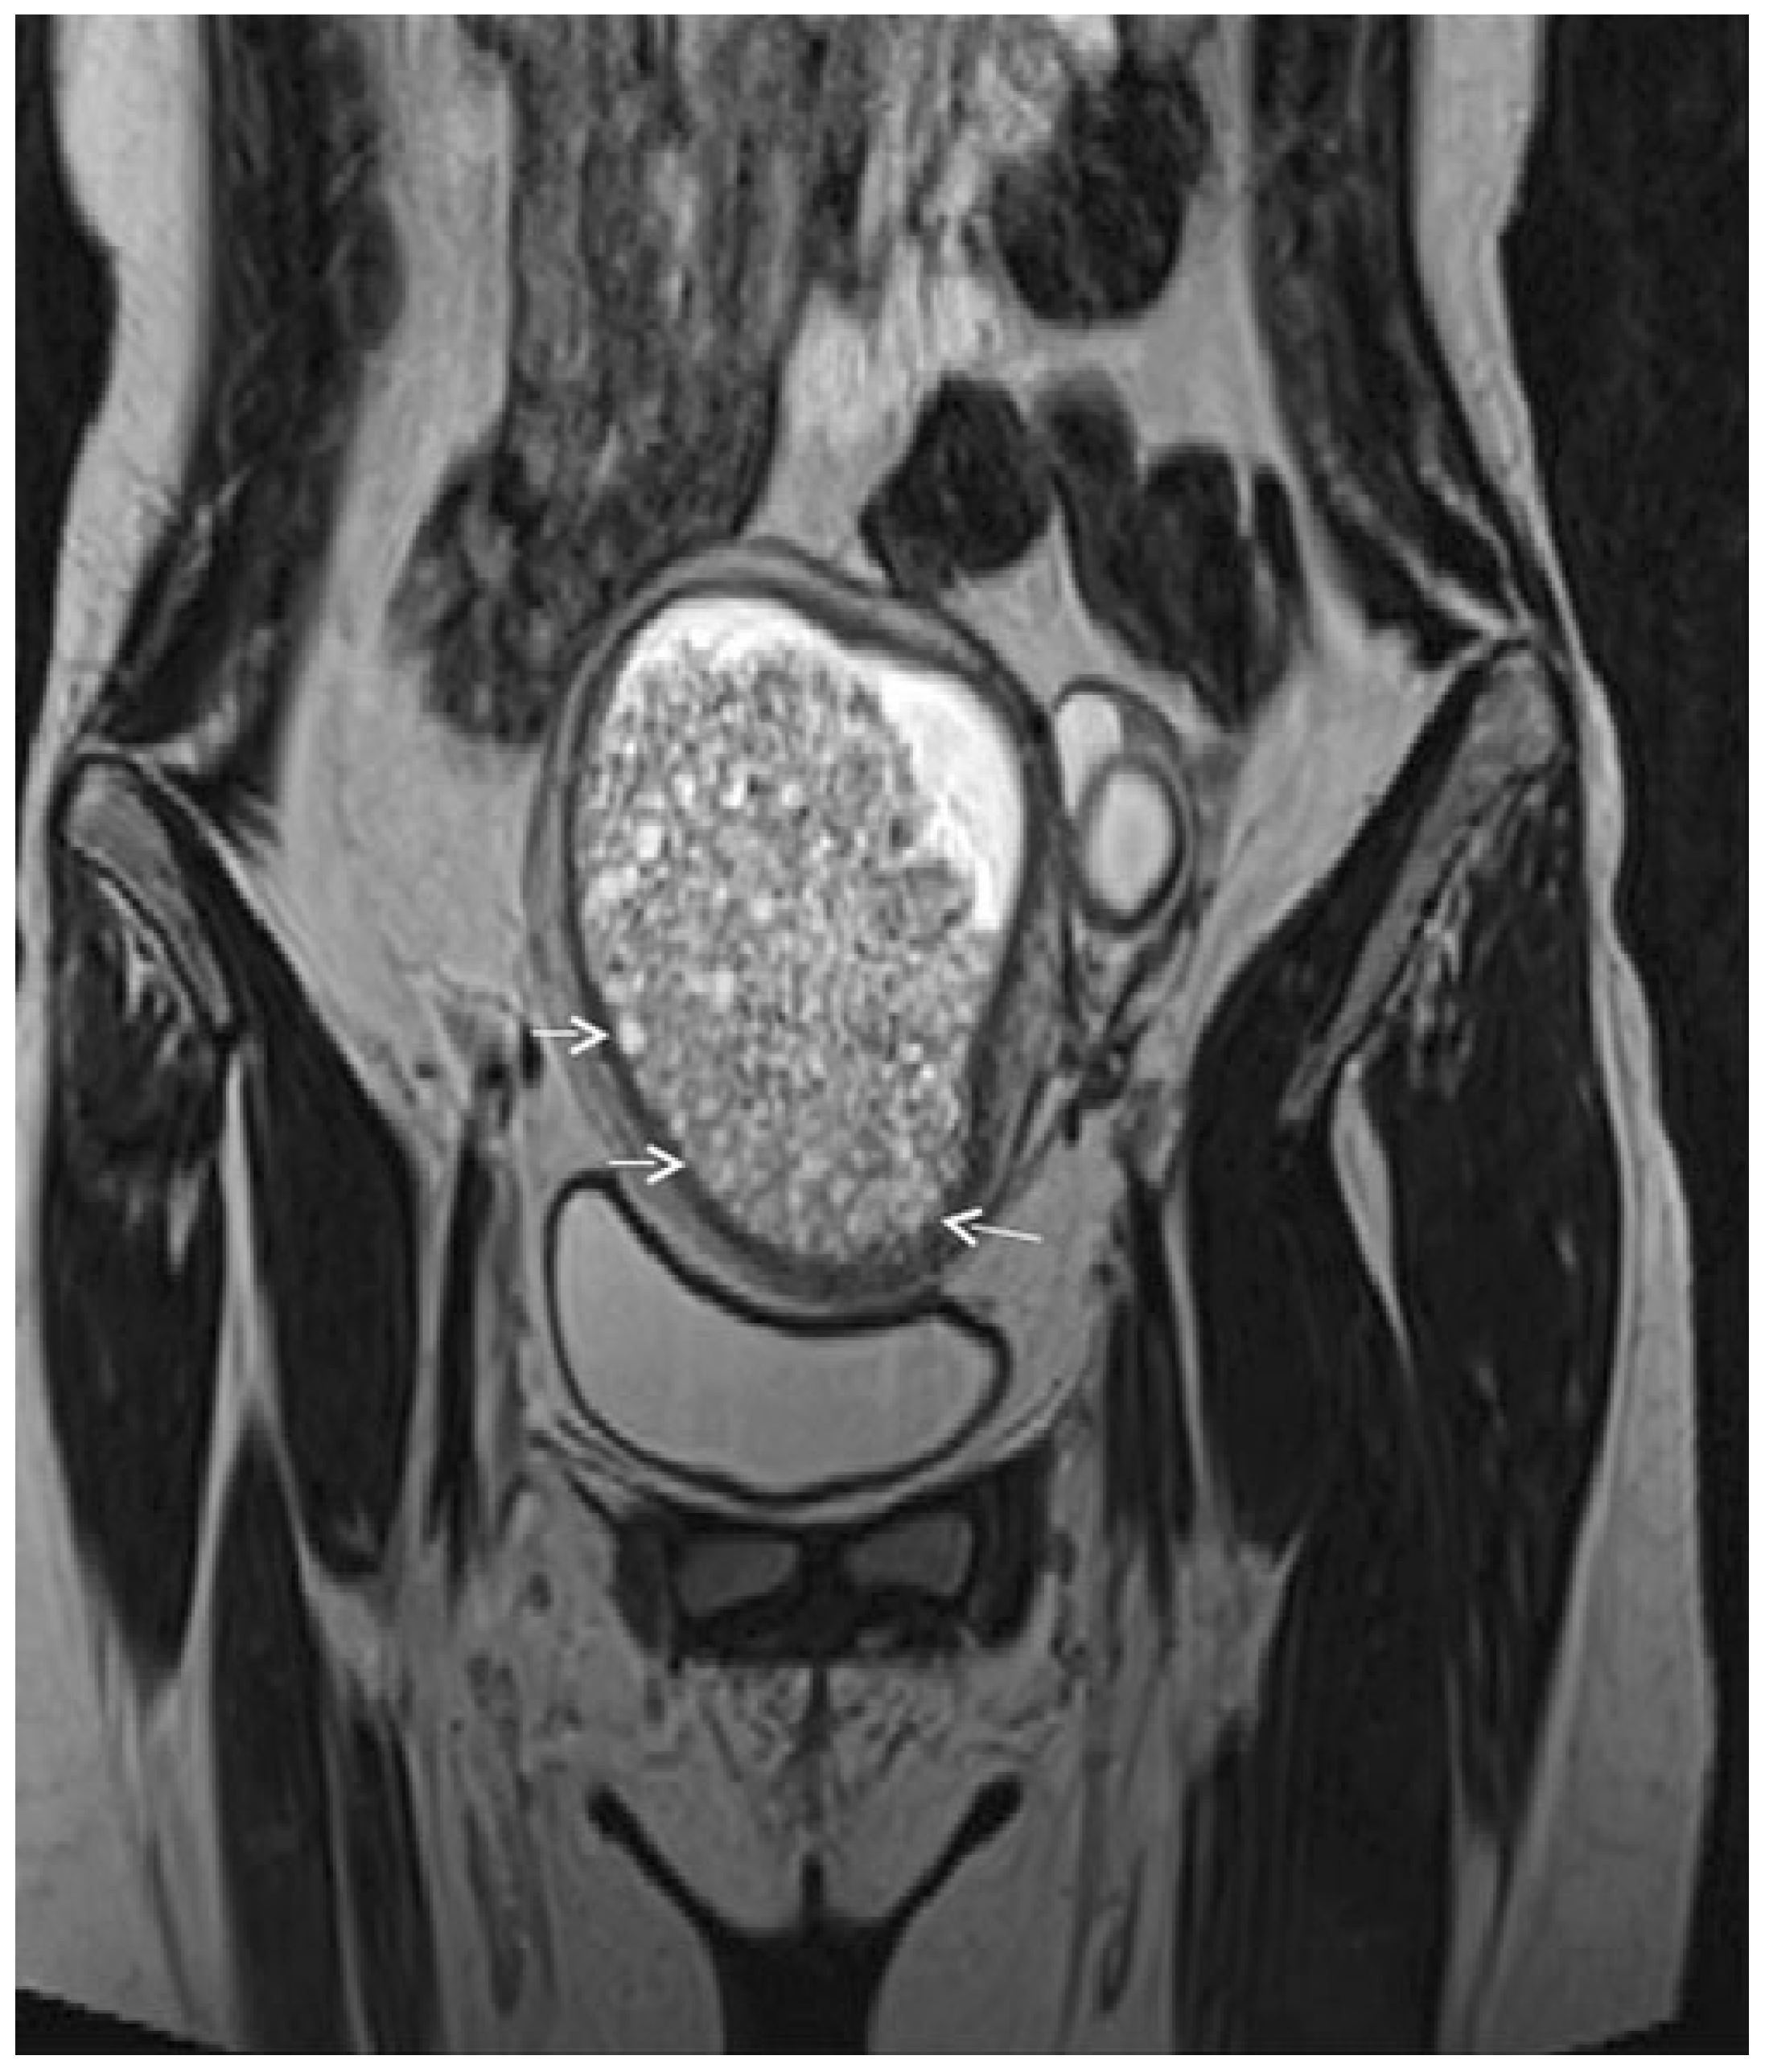

3.2.2. Imaging

3.2.3. Mimickers of Malignancy